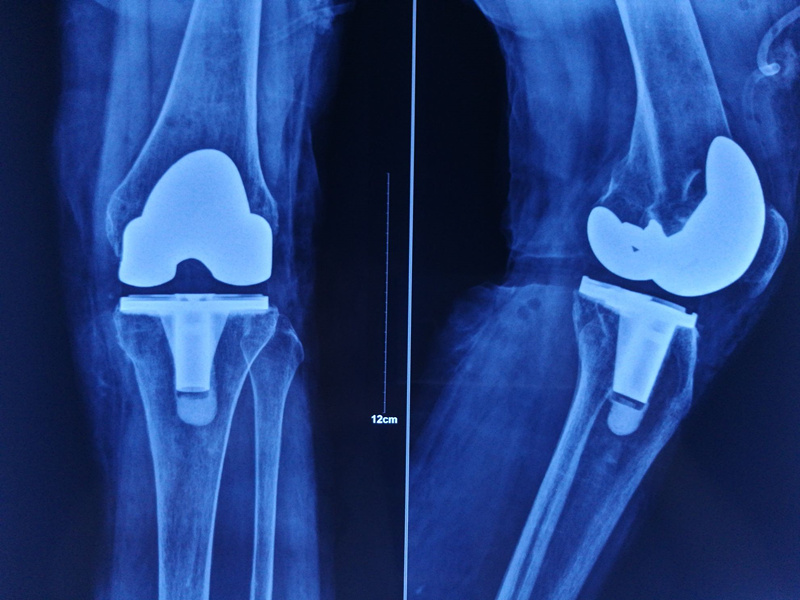

5月26日,我院骨科团队为81岁高龄患者进行全膝关节置换手术。省级大三甲医院骨科教授莅临我院,共同研讨膝关节疾病,省市专家联手,开启了我院全方位诊治膝关节疾病新模式。

按照这一模式,对膝关节疾病尤其骨关节炎进行全方位一条龙的规范治疗。从早期的宣教、保守治疗,到中期的胫骨高位截骨术(HTO)及单髁置换术(UKA),到最后终末期的全膝关节置换术(TKA)。膝关节骨关节炎病人到了我院,即可对号入座,精准治疗。